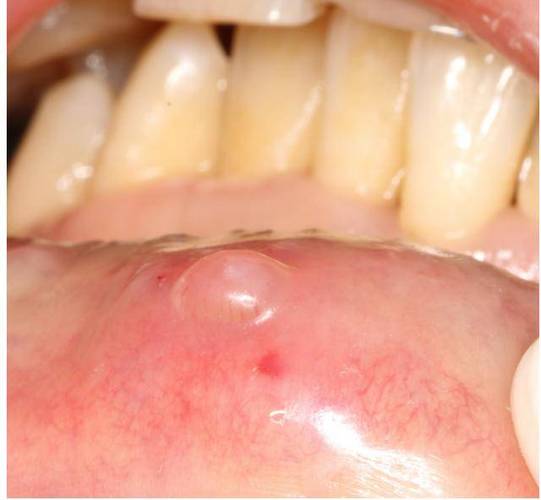

最常见的原因:口腔粘液腺囊肿

这是口腔内长小水泡最常见的原因,占了绝大多数。

- 成因:我们的口腔黏膜下有无数微小的唾液腺(粘液腺),当这些腺体的导管因为外伤(如咬到、烫伤、吃东西划伤)或堵塞(如粘稠的分泌物堵住了出口)时,分泌的唾液无法正常排出,就会在腺体周围形成一个充满透明或半透明粘液的小囊肿。

- 外观:通常是单个、圆形、半透明或淡黄色、像水珠一样的小泡。

- 大小:直径一般不超过1厘米,大小不固定,时大时小。

- 位置:最常见于下唇内侧,也可能出现在舌腹、颊粘膜等部位。

- 感觉:通常不痛,除非破裂,吃东西时不小心咬到会感到疼痛。

- 变化:有时会自行破裂,流出粘稠液体后变小甚至消失,但不久后又可能在原位复发。